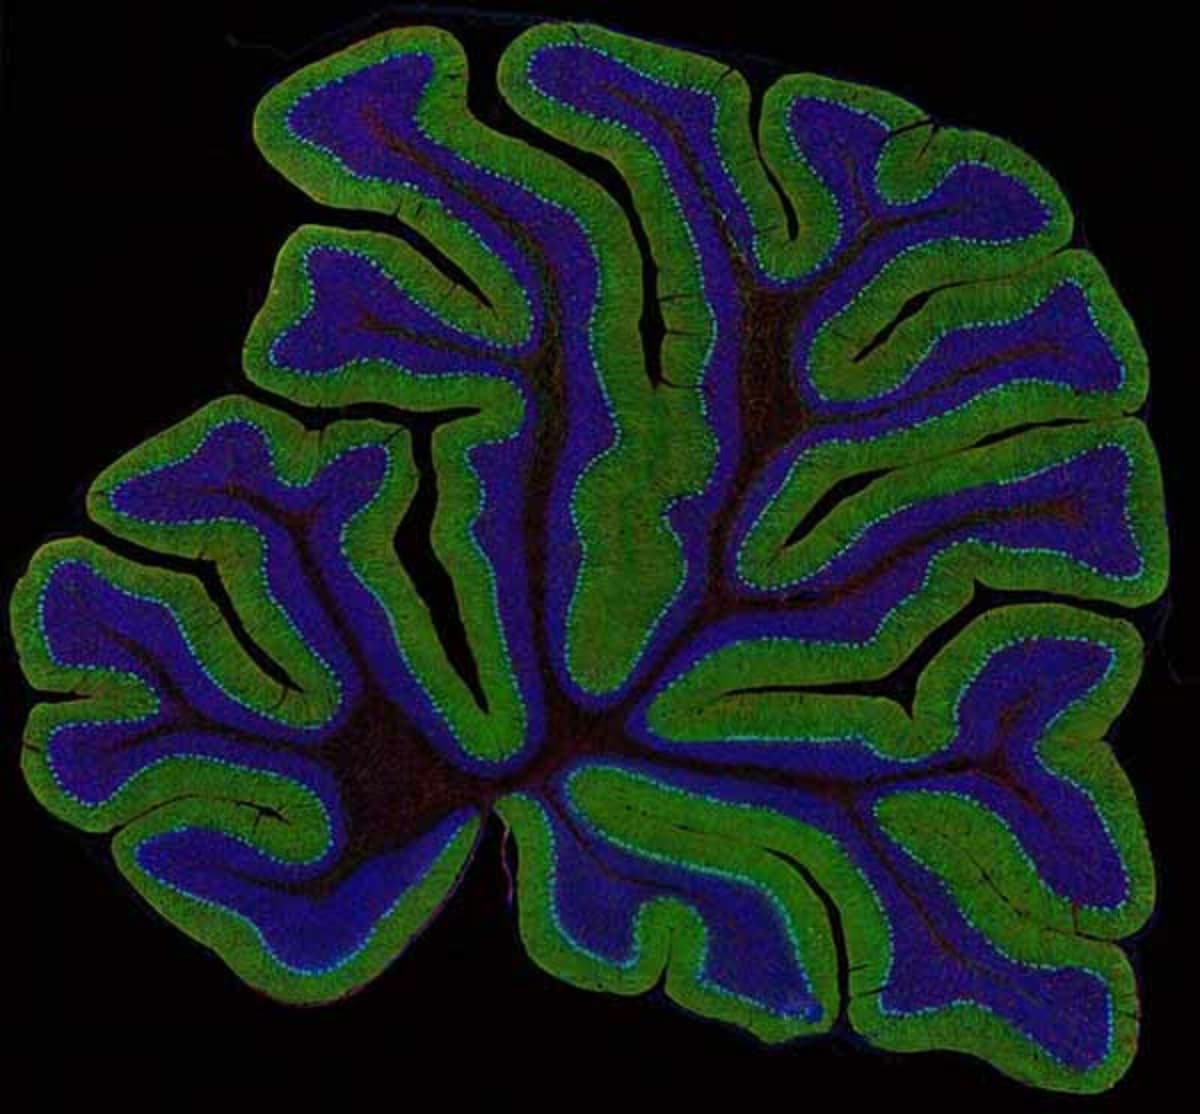

The projects will seek to measure four different aspects of the brain’s activity: electrical activity, neurochemical activity, metabolic activity and gene activity. The technological strategies include advances in microscopy, brain imaging, sensors based on nanotechnology, and neural prosthetics, explained UC San Diego’s Ralph Greenspan, who co-directs Cal-BRAIN with Paul Alivisatos of the Lawrence Berkeley National Laboratory